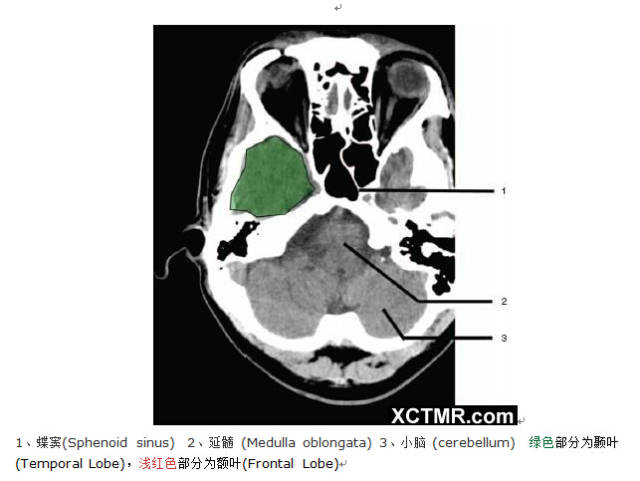

颅脑CT彩色解剖